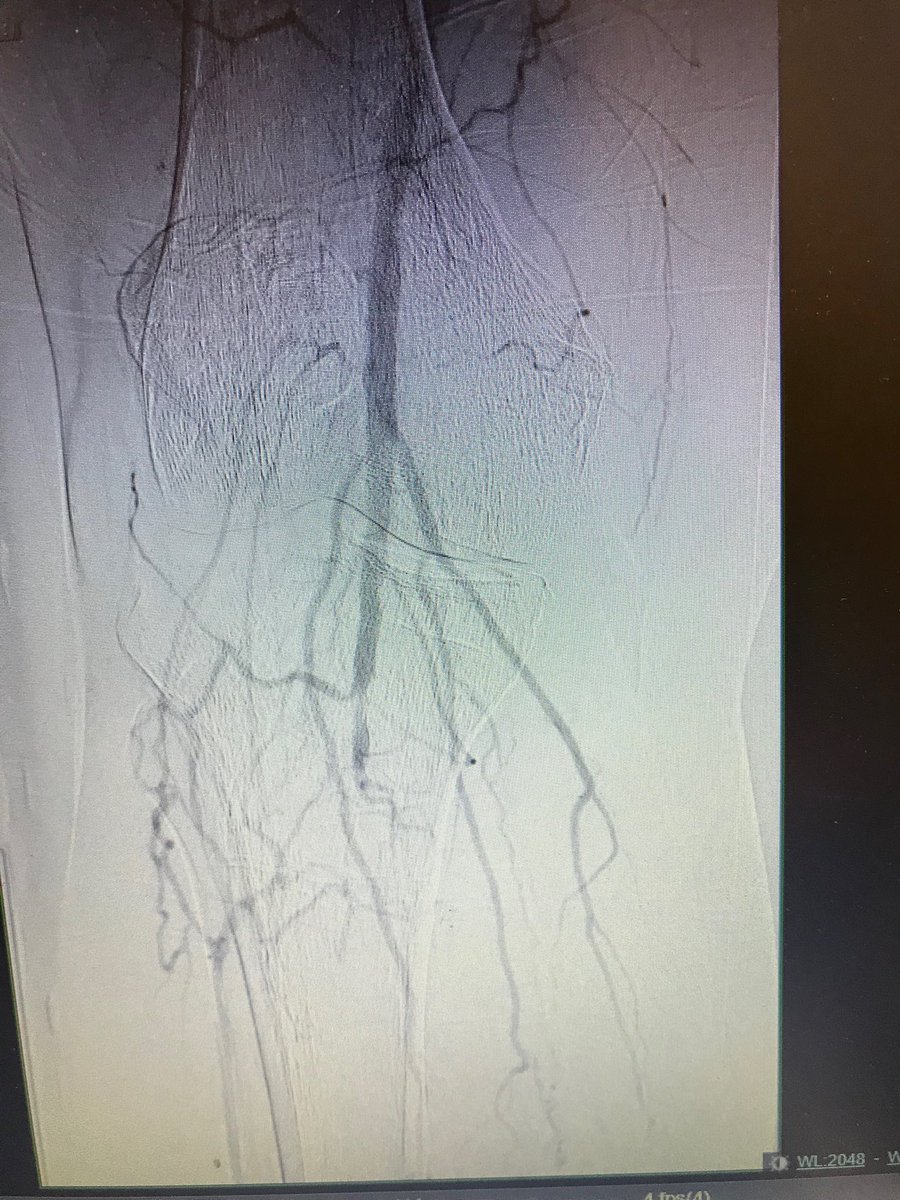

#pad #cardiotwitter#cto. 55 m dm, claudicant.no runoff.#pedalaccess , Antero and retro approach. #doubleballoon , #safari .#dcb.#supera .good dp pulse. Home same day.

istentem's tweet image. #pad #cardiotwitter#cto. 55 m dm, claudicant.no runoff.#pedalaccess , Antero and retro approach. #doubleballoon , #safari .#dcb.#supera .good dp pulse. Home same day.